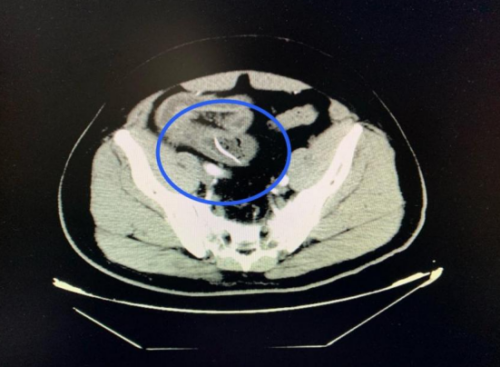

)急诊医学科就诊。医生详细询问病情并进行体格检查后,立即安排了腹部 CT 扫描。CT结果显示:回肠高密度影,考虑尖锐异物并小肠穿孔、腹膜炎。结合阳宇军三天前吃甲鱼的经历,医生高度怀疑是误吞甲鱼骨导致了肠穿孔。

CT扫描可见一尖锐的鱼刺状异物